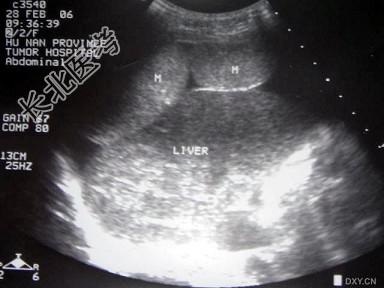

- 单项选择题图中所示肿瘤最有可能是哪个部位的占位   (   )

A、肝脏

B、膈肌

C、胰腺

D、腹膜

E、肠道